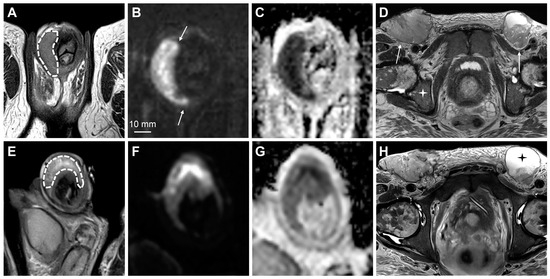

3.3. Role of MRI in Staging of Penile Cancer